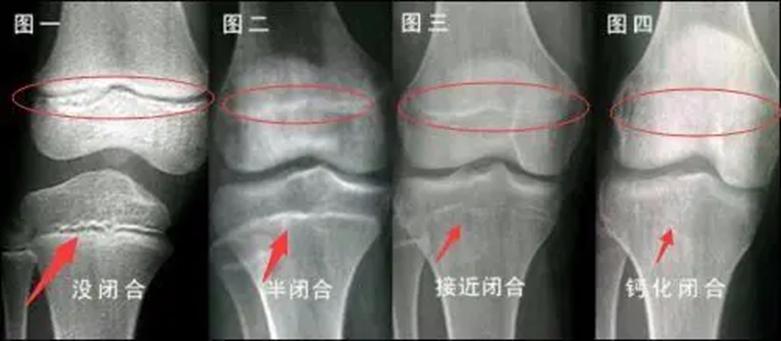

骨骺线闭合过程示意图 图源:网络

人体骨骼在发育的过程中, 骨头两端的软骨中出现的骨化点称为骨骺。 在人体骨骼还未成熟时,一些骨骼还呈现软骨的状态。当身体发育完成,这一部分软骨就会完全骨化,变成一条紧密的缝。

一般在 16~20 岁之间人体会完全长成,骨骺线闭合,身高固定下来,当然也会因为个体的差异而有所不同。

骨骺有四个生长阶段: 生发期、增殖期、塑形期以及闭合期。 骨骺的发育受到很多因素的影响,但是生长阶段不会因为骨的发育而有所提前。所以可以从 骨骺的生长时期情况 判断骨是否还在生长。